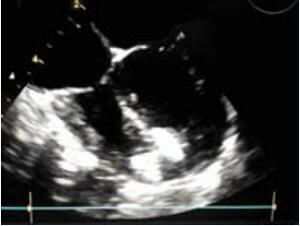

在超声透声图像欠佳或者发生与心尖部缺损封闭相关的其他并发症时,特别是成人患者、数个肌部缺损情况下,可以考虑“杂交”方法和介入方法结合进行(图10-51,图10-52)。笔者遇到一例成人肌部室间隔缺损患者,利用杂交手术的方法由于超声图像不清晰导丝无法通过缺损(胸骨正中小切口,心脏上部难以拖出、操作过程中TEE图像无法显示缺损)。

3个月后,介入医生成功关闭了患者的肌部缺损。其中的经验非常重要。应该结合这两种微创方法,为每一个个体选择最好的方法。这是笔者对微创的结合概念的理解。